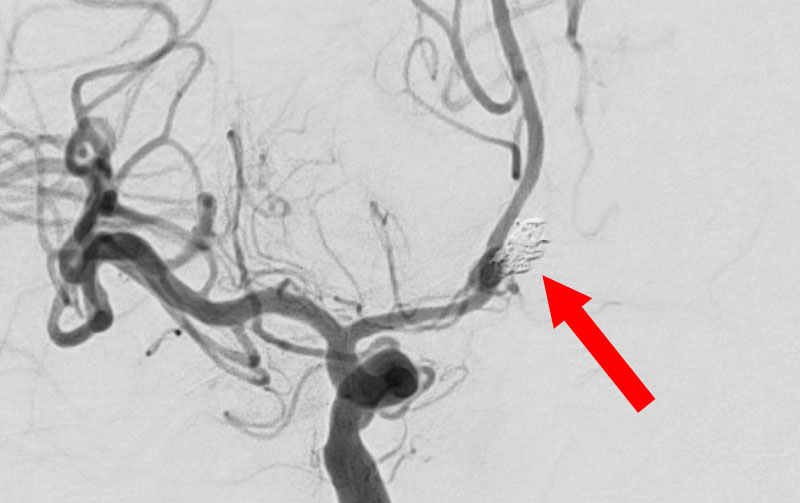

'25年11月

左内頚動脈脳動脈瘤

60代

大阪府の病院

No.1595 手術前

No.1595 手術後